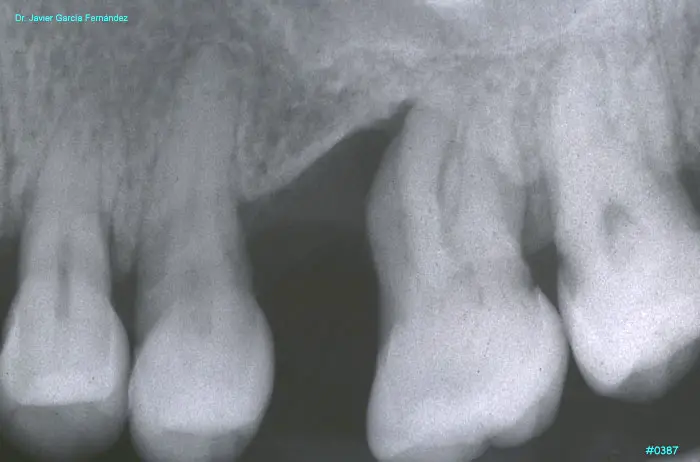

ATLAS DE CIRUGIA PERIODONTAL

imagen 439